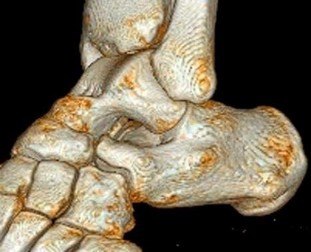

A 30-year-old female sustains a midfoot injury after falling from a horse. Radiographs demonstrate diastasis between the bases of the 1st and 2nd metatarsals. In a normal anatomic state, the native Lisfranc ligament originates and inserts on which two bony structures?

Explanation

The Lisfranc ligament is a stout, obliquely oriented intra-articular ligament that acts as the primary stabilizer of the second tarsometatarsal joint complex. It connects the lateral aspect of the medial cuneiform to the medial aspect of the base of the second metatarsal. Importantly, there is no direct ligamentous connection between the bases of the first and second metatarsals.